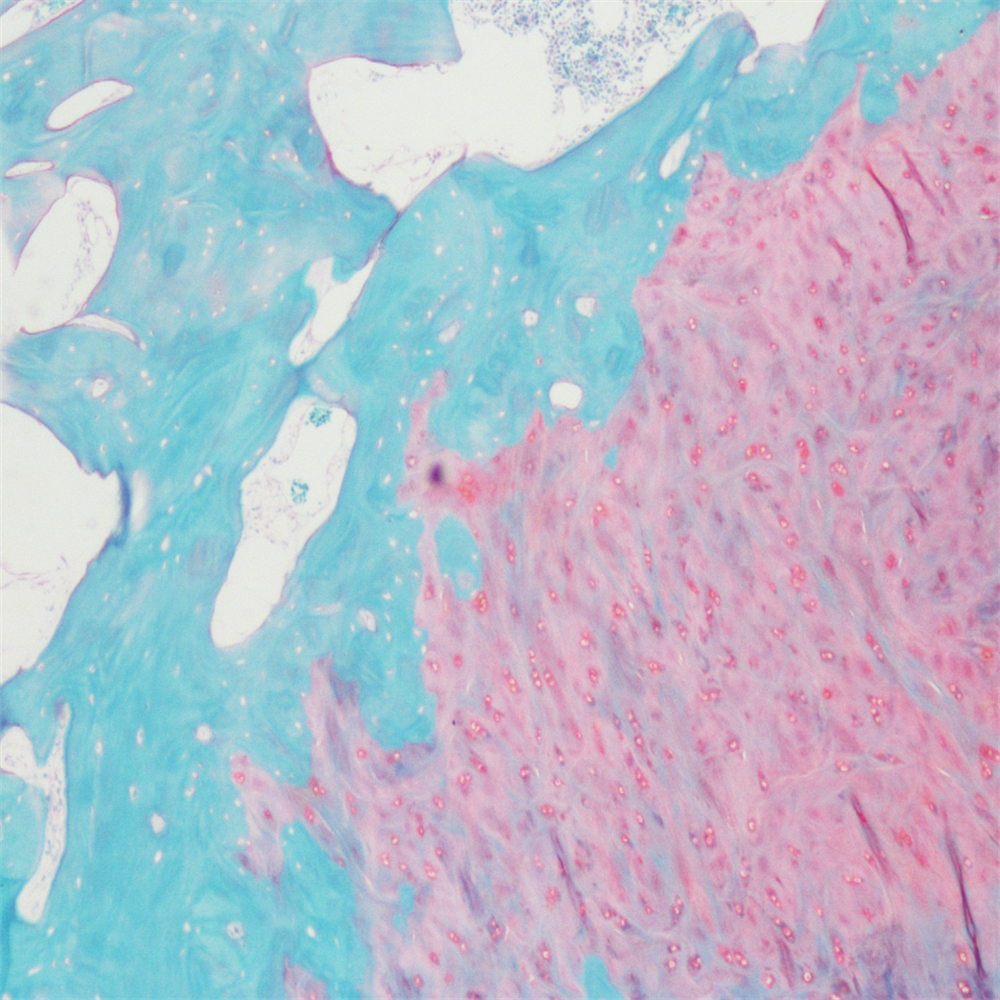

番红-固绿染色

番红-固绿染色(软骨)在涉及关节软骨及软骨下骨的形态学研究中,常需联合使用多种染料以显示其组织学结构。其中,起源于上世纪60年代的番红O(safranin O)-固绿(fast green)染色因可以直观反映关节软骨、软骨下骨和骨组织的结构而备受青睐。软骨呈红色,成骨呈绿色。

番红-固绿(软骨)染色法的染色原理在于嗜碱性的软骨和碱性染料番红O结合呈现红色,嗜酸性的骨和酸性染料固绿结合而成绿色或者蓝色,与呈现红色的软骨对比鲜明,从而将软骨组织和骨组织区分开。番红O是一种结合多阴离子的阳离子染料,其显示软骨组织是基于阳离子染料与多糖中阴离子基团(硫酸软骨素或硫酸角质素)结合。番红O着色与阴离子的浓度近似成正比关系,间接反映基质中蛋白多糖的含量和分布。当软骨收到损伤时,软骨中的糖蛋白会释放出来,使基质成分分布不均匀,从而导致番红O淡染或不着色。通过图像分析软件可以对番红O染色的软骨基质进行定量分析。固绿与胶原纤维结合,不宜褪色。

<番红固绿-骨>